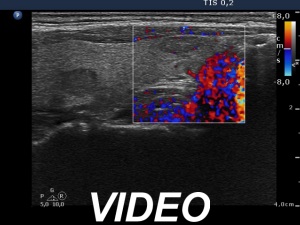

Ultrasonography. The thyroid was echonormal and contained multiple nodules including a hypoechogenic one in the lower pole of the right lobe presenting coarse calcifications. The nodule in the lower part of the left lobe was also noteworthy.

Comment. Although the cytological pattern of the right lesion corresponds to a follicular tumor if we consider the ultrasound presentation than the risk of a follicular neoplasia is very low: the lesion exhibited neither halo sign nor perinodular blood flow. It means that there were not present any signs of a capsule. In such cases the risk of a follicular tumor is less than 5%.